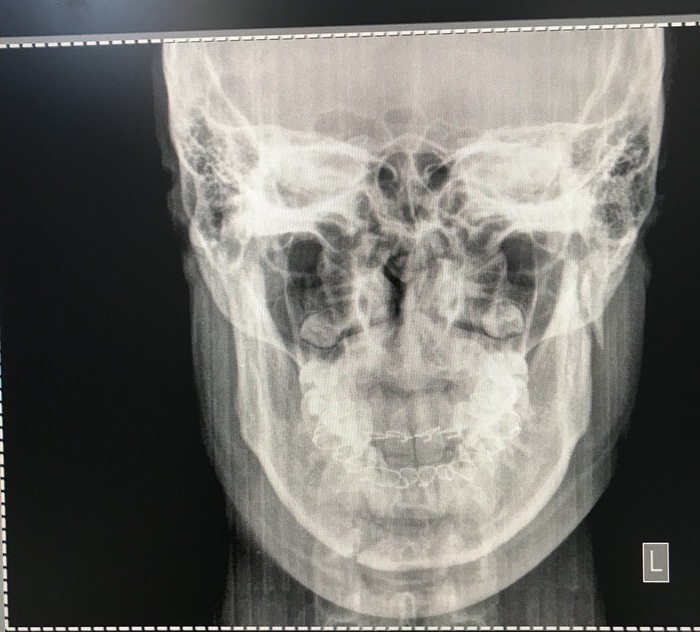

Снимают ли пластины после операции на нижней челюсти

Двухчелюстная операция, гениопластика и ринопластика — именно к этим хирургическим вмешательствам обратилась читательница Cosmo. Почему девушка решилась на это и как выбрала врача, что стоит знать о постоперационном периоде и на какие моменты стоит обратить внимание — узнай из ее личной истории.

Мой путь к подобным изменениям во внешности начался еще в 2010 году, когда я первый раз поставила брекеты. На тот момент об ортогнатических операциях (иными словами, о хирургическом воздействии на челюсть) знали, мне кажется, только самые профессиональные стоматологи-ортодонты, к которым мой ортодонт, к сожалению, не относился. В итоге – минус 2 верхних зуба. Да, зубы стали прямыми, но прикус как был странным, таким и остался. Это только потом я узнала такие слова, как дистальный и мезиальный, но это случилось сильно позже. Об этом расскажу подробнее.

В 2015 году я начала задумываться над тем, что мой профиль, мягко говоря, далек от идеала и сделать ринопластику было бы совсем неплохо. В профиль нос предательски торчал впереди челюсти, и мне это не нравилось. Я стала прикидывать стоимость операции и наткнулась на форум о пластической хирургии, где заметила ветку о гениопластике (то есть костном перемещении подбородка), изучила и подумала, что, возможно, это как раз мой случай. Я зарегистрировалась, написала в поддержку хирургов, чтобы они подсказали, что мне лучше сделать — нос или подбородок. И тут на удивление мне пришли ответы от нескольких хирургов, они единогласно рекомендовали для начала поправить прикус.

Для меня было важно, чтобы ортодонт умел работать с такими, как я. Что я имею в виду? Мой прикус был дистальным: нижняя челюсть меньше верхней и уходит назад. От этого в профиль получаешь эффект скошенного подбородка и так называемое птичье лицо. Мы, дистальщики, почти всегда на фотографиях выдвигаем челюсть вперед, чтобы на фото получалось немного гармоничнее. Мезиальный прикус — нижняя челюсть выдвинута сильно вперед. Яркий пример – Ксения Собчак.